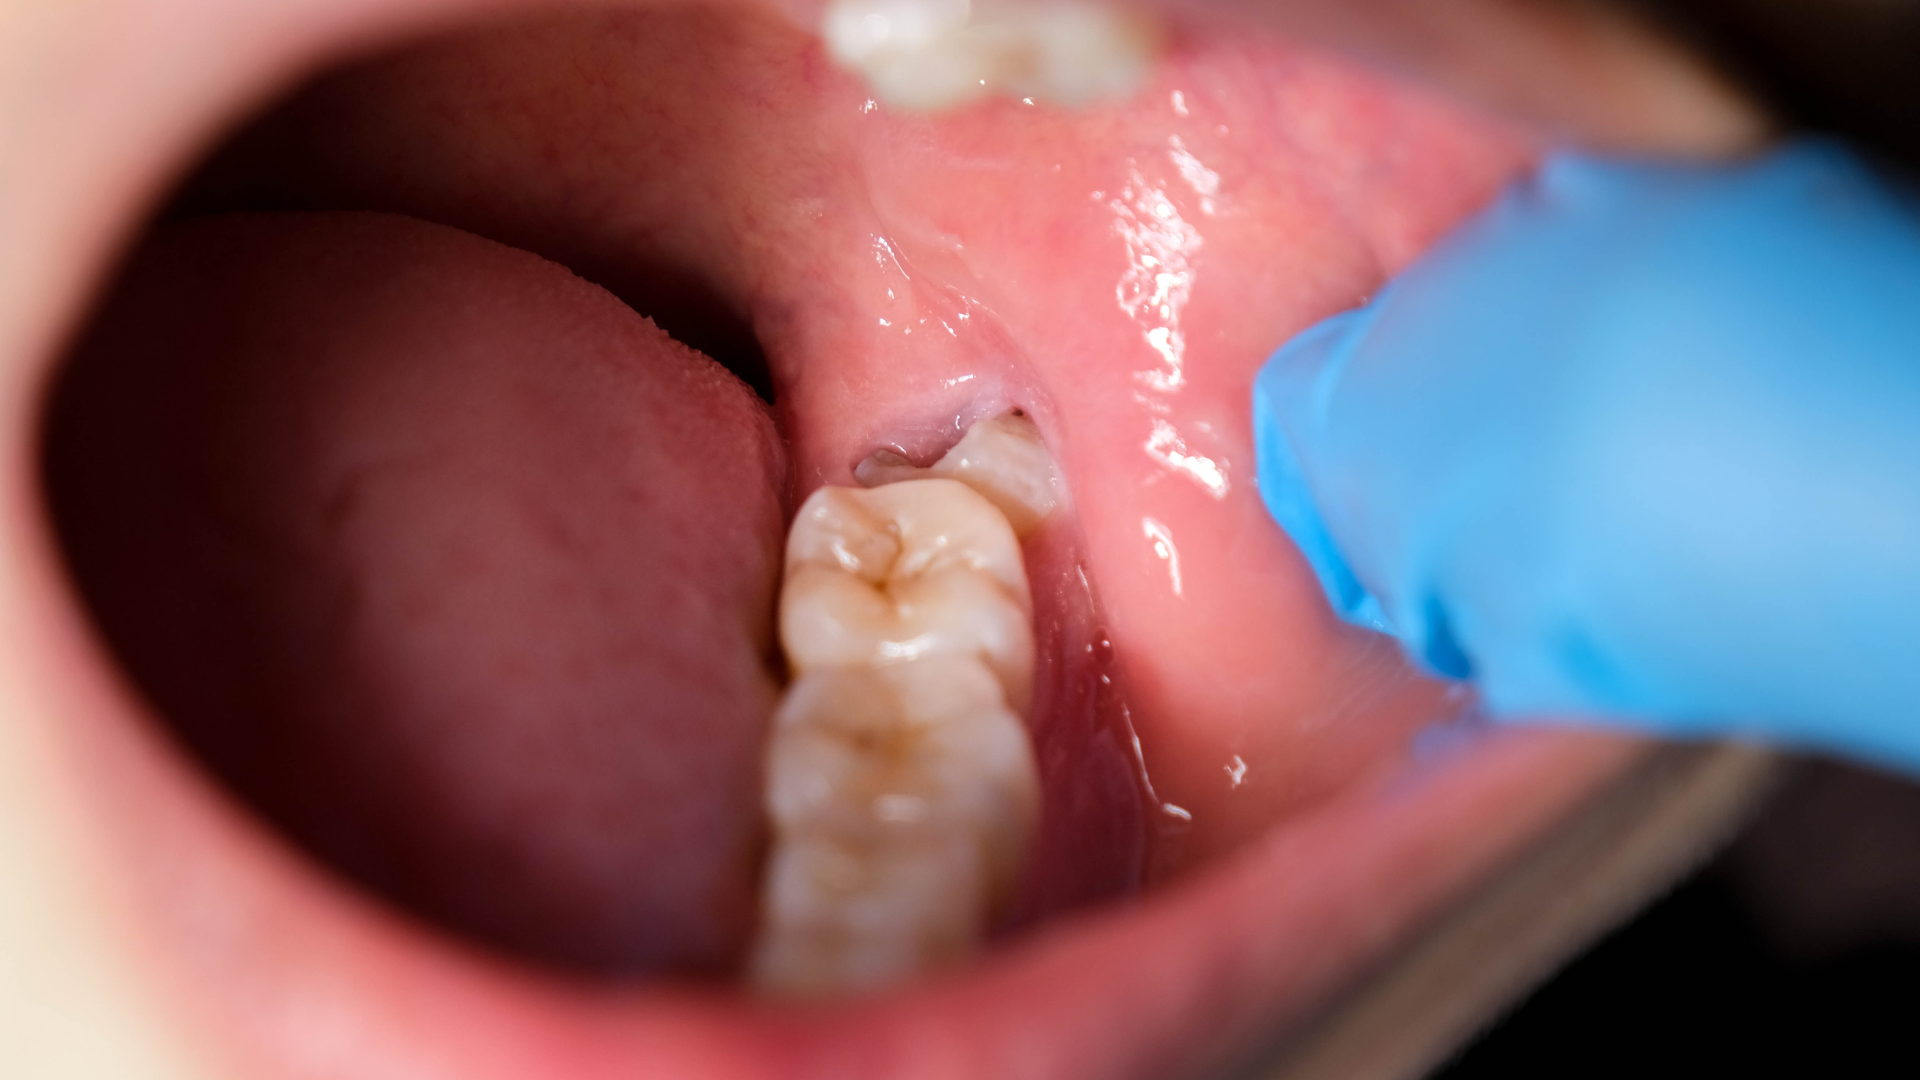

What Exactly Is Pericoronitis?

Picture this: a tooth partially breaks through the gum, creating a small pocket where food particles and bacteria can accumulate. This space becomes nearly impossible to clean properly, leading to inflammation, swelling, and that familiar pulsating pain that can radiate to your ear, throat, or jaw.